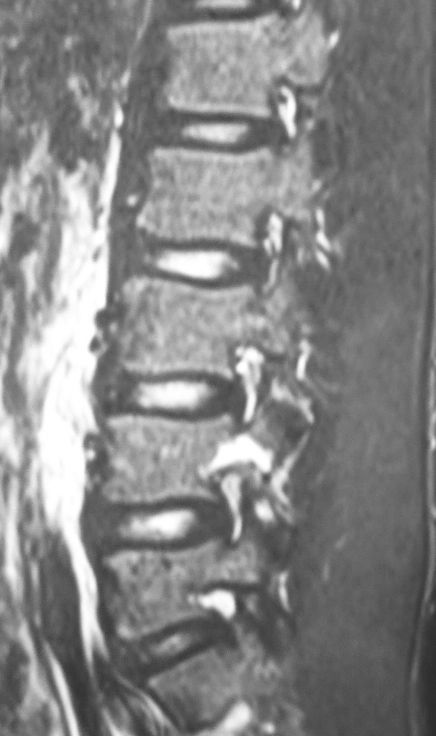

11月の初診時には、単純X線像・CT像とも明らかな異常所見を認めませんでした。しかし慢性腰痛が気持ち悪かったのでMRIを施行したところ、L4の左椎弓に分離症の所見を認めました。

その後、ダーメンコルセットを作成して3ヶ月間常用とした上で、野球・スポーツ・体育の授業を完全に禁止しました。2ヵ月ぐらいしてから痛みが軽快し、本日腰椎MRIで最終確認を行いました。

11月のMRIでは高輝度だった左椎弓が、本日のMRIでは正常な輝度になっていることがはっきり分かります。めでたく、本日でダーメンコルセットを除去してスポーツ復帰を許可しました。

通常、単純X線像やCTで腰椎分離症の診断・治療を行うことが多いと思いますが、MRIの方が感度が高くて早期治療や治癒の判定には有効だと思います。